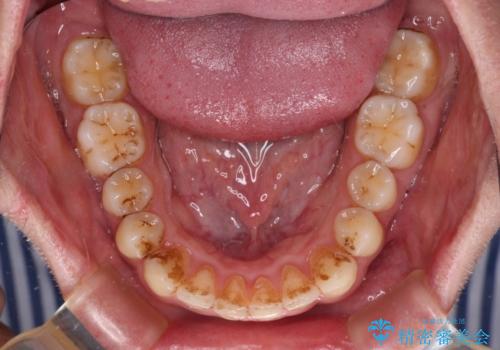

前歯のデコボコをスッキリ改善 インビザライン矯正

- 上下前歯のデコボコを気にして来院された患者様です。

全体的に叢生は軽度であったため、インビザラインにて矯正治療を行うこととしました。

デコボコの改善はもちろん、下顎前歯が隠れてしまうディープバイトも一緒に改善することができ、奥歯への負担を軽減することができました。